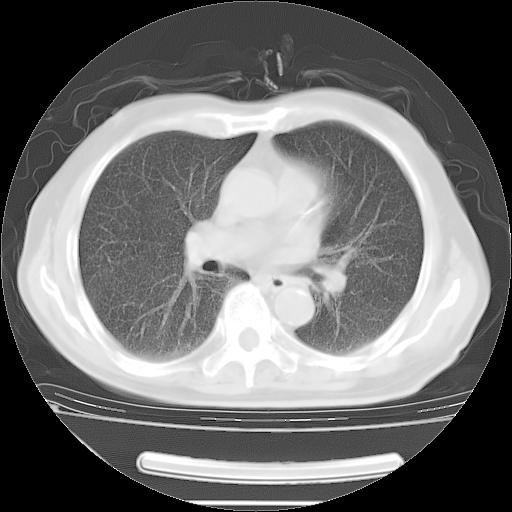

胸腹部CT,诊断意见:左上肺叶钙化灶、左侧胸膜局限性增厚并钙化、胆囊炎。描述部分肺组织呈磨玻璃样改变。